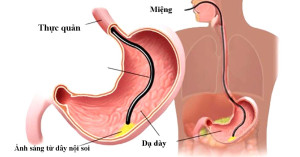

Việc gây mê khi nội soi dạ dày rất cần thiết nếu bác sĩ cần thực hiện các thủ thuật can thiệp không gây đau và an toàn hơn.